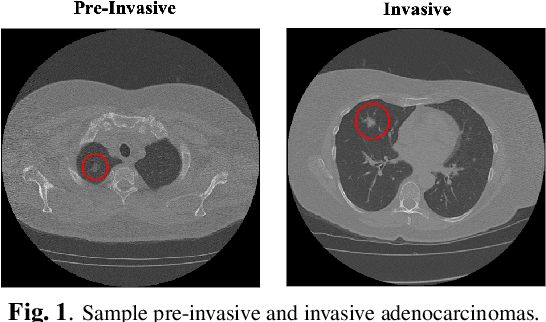

Abstract:The paper proposes a novel hybrid discovery Radiomics framework that simultaneously integrates temporal and spatial features extracted from non-thin chest Computed Tomography (CT) slices to predict Lung Adenocarcinoma (LUAC) malignancy with minimum expert involvement. Lung cancer is the leading cause of mortality from cancer worldwide and has various histologic types, among which LUAC has recently been the most prevalent. LUACs are classified as pre-invasive, minimally invasive, and invasive adenocarcinomas. Timely and accurate knowledge of the lung nodules malignancy leads to a proper treatment plan and reduces the risk of unnecessary or late surgeries. Currently, chest CT scan is the primary imaging modality to assess and predict the invasiveness of LUACs. However, the radiologists' analysis based on CT images is subjective and suffers from a low accuracy compared to the ground truth pathological reviews provided after surgical resections. The proposed hybrid framework, referred to as the CAET-SWin, consists of two parallel paths: (i) The Convolutional Auto-Encoder (CAE) Transformer path that extracts and captures informative features related to inter-slice relations via a modified Transformer architecture, and; (ii) The Shifted Window (SWin) Transformer path, which is a hierarchical vision transformer that extracts nodules' related spatial features from a volumetric CT scan. Extracted temporal (from the CAET-path) and spatial (from the Swin path) are then fused through a fusion path to classify LUACs. Experimental results on our in-house dataset of 114 pathologically proven Sub-Solid Nodules (SSNs) demonstrate that the CAET-SWin significantly improves reliability of the invasiveness prediction task while achieving an accuracy of 82.65%, sensitivity of 83.66%, and specificity of 81.66% using 10-fold cross-validation.

Abstract:Lung cancer is the leading cause of mortality from cancer worldwide and has various histologic types, among which Lung Adenocarcinoma (LAUC) has recently been the most prevalent. Lung adenocarcinomas are classified as pre-invasive, minimally invasive, and invasive adenocarcinomas. Timely and accurate knowledge of the invasiveness of lung nodules leads to a proper treatment plan and reduces the risk of unnecessary or late surgeries. Currently, the primary imaging modality to assess and predict the invasiveness of LAUCs is the chest CT. The results based on CT images, however, are subjective and suffer from a low accuracy compared to the ground truth pathological reviews provided after surgical resections. In this paper, a predictive transformer-based framework, referred to as the "CAE-Transformer", is developed to classify LAUCs. The CAE-Transformer utilizes a Convolutional Auto-Encoder (CAE) to automatically extract informative features from CT slices, which are then fed to a modified transformer model to capture global inter-slice relations. Experimental results on our in-house dataset of 114 pathologically proven Sub-Solid Nodules (SSNs) demonstrate the superiority of the CAE-Transformer over the histogram/radiomics-based models and its deep learning-based counterparts, achieving an accuracy of 87.73%, sensitivity of 88.67%, specificity of 86.33%, and AUC of 0.913, using a 10-fold cross-validation.